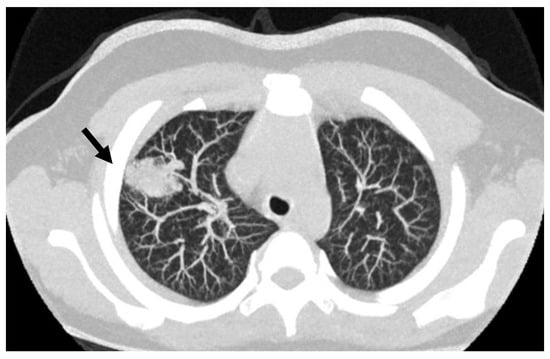

7. Arterovenous Malformations (AVM)